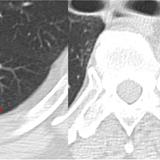

LUL Collapse

Album: LUL Collapse